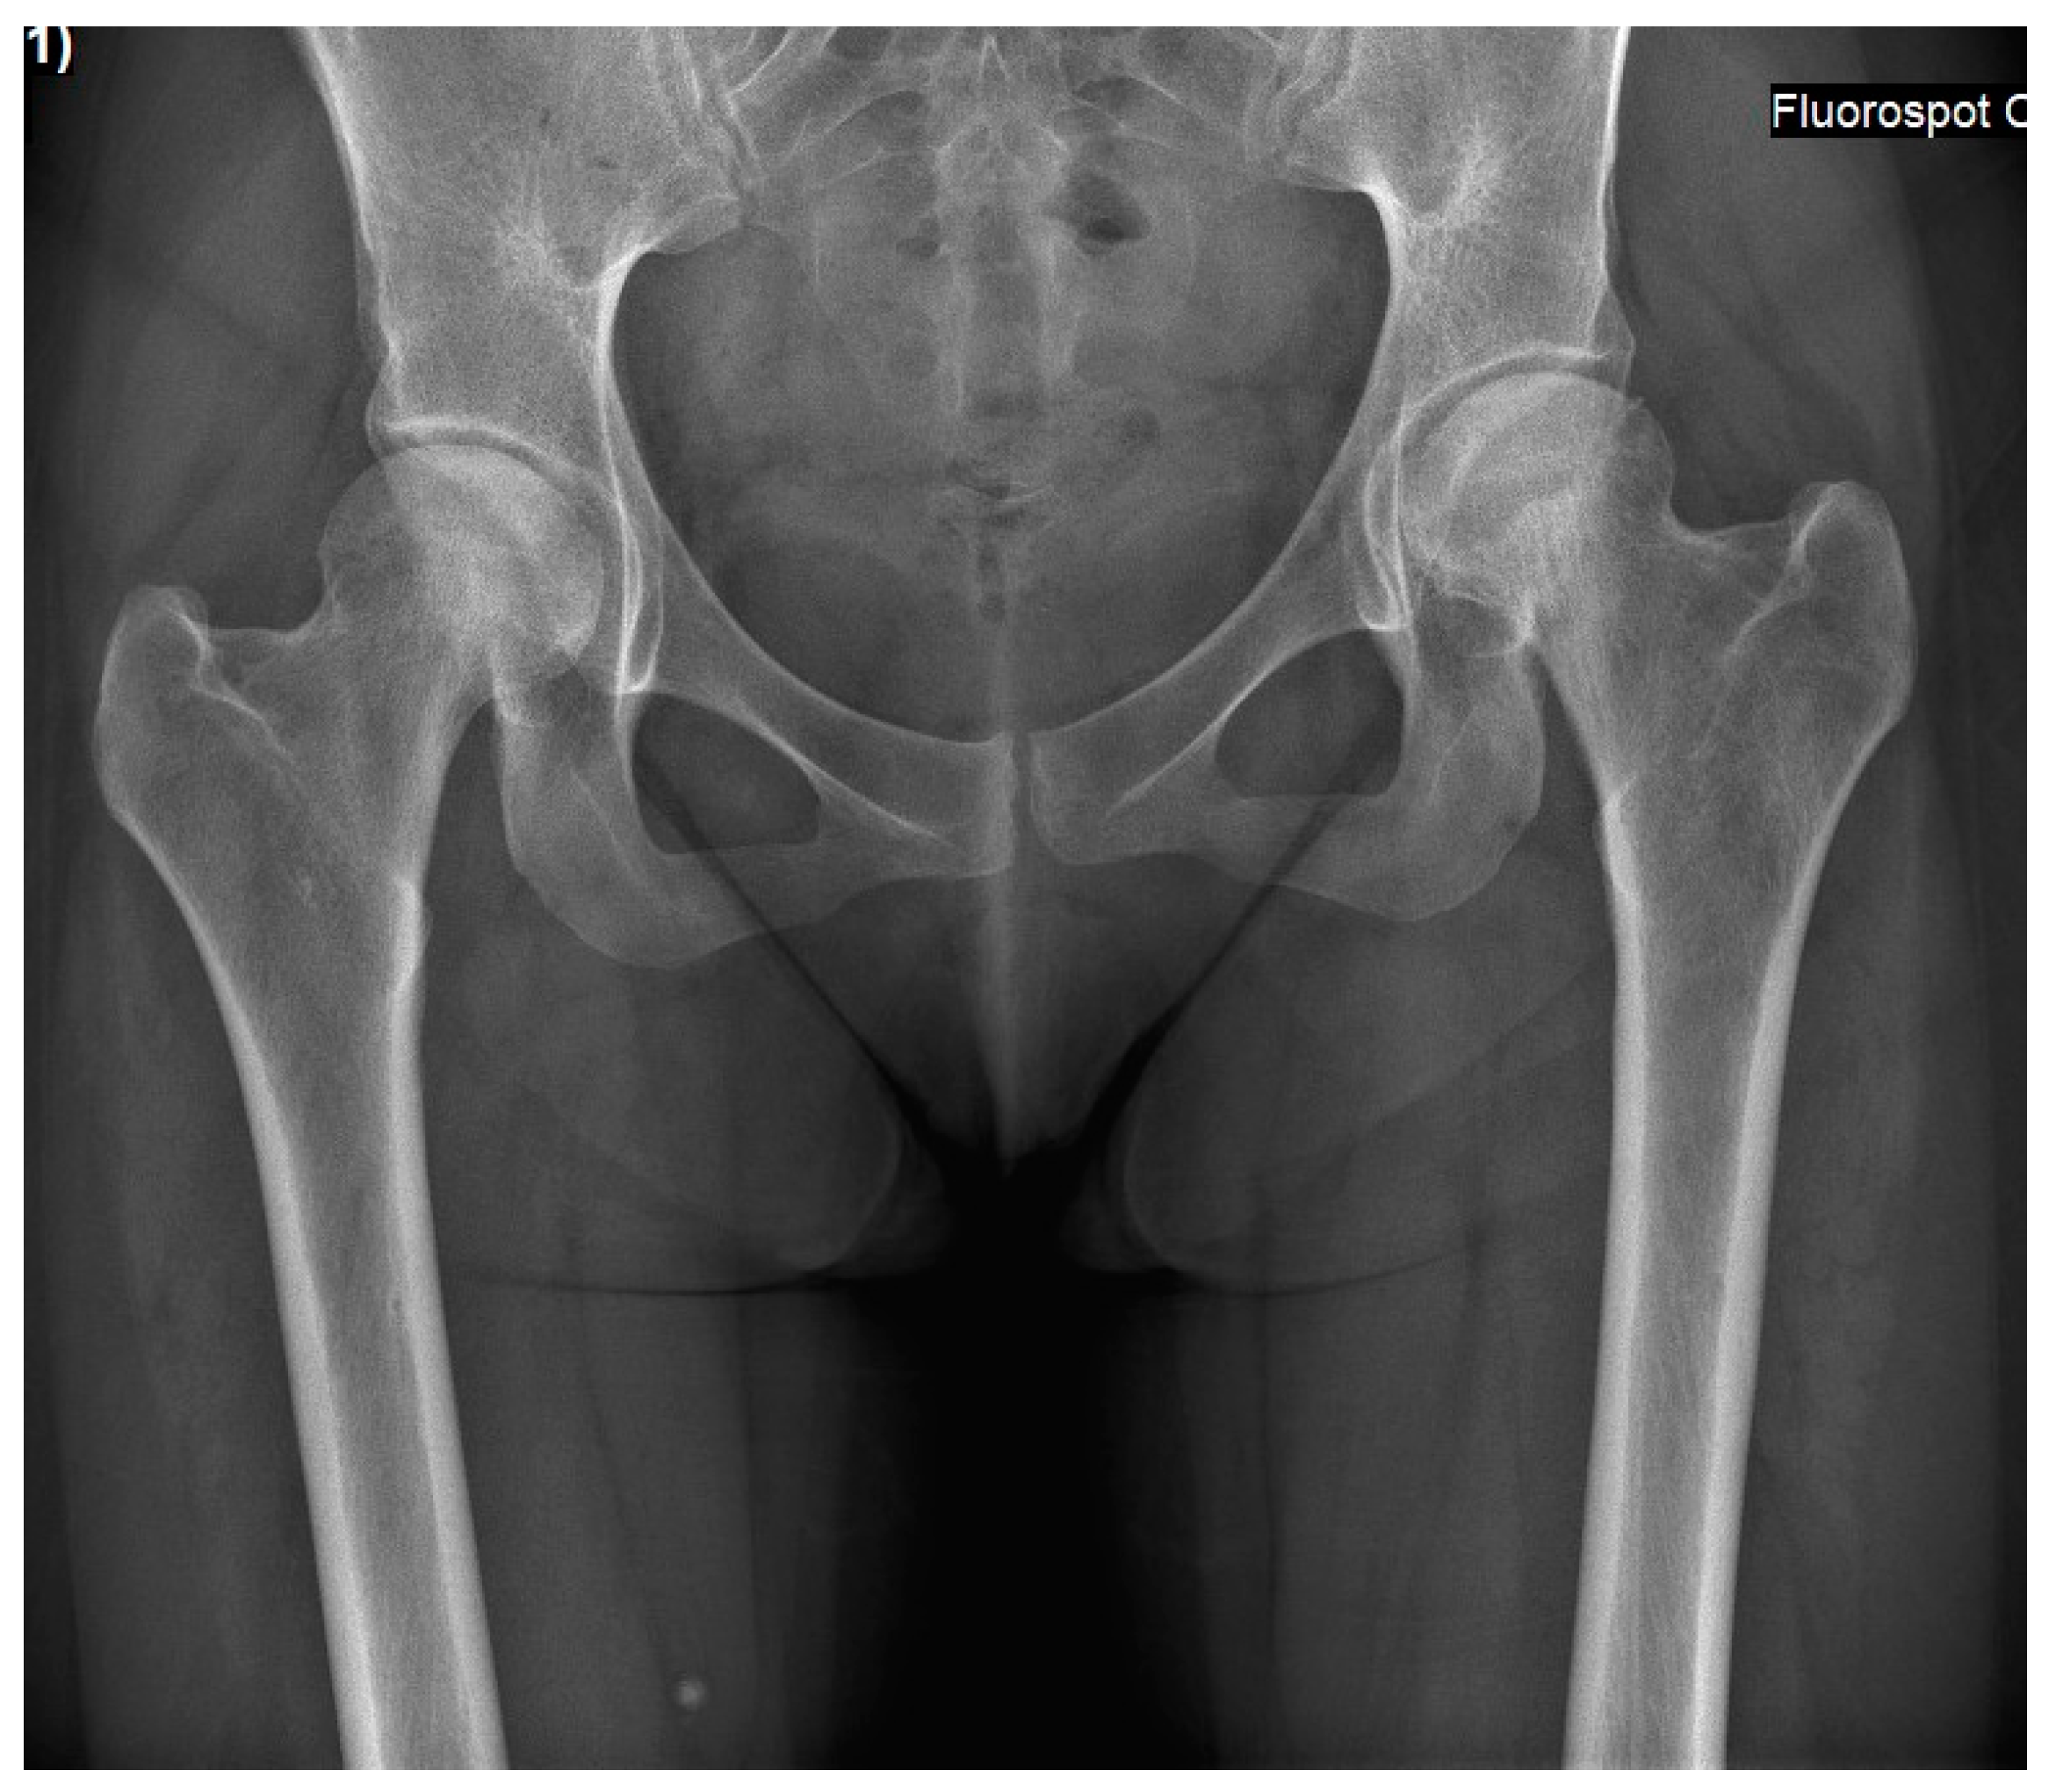

Figure 3.

An antero-posterior pelvis X-ray of Case 2 was performed a few days after pain started, and it was already bilateral. These findings present a pre-collapse radiographic stage, where both femoral heads are spherical, and joint space is preserved.